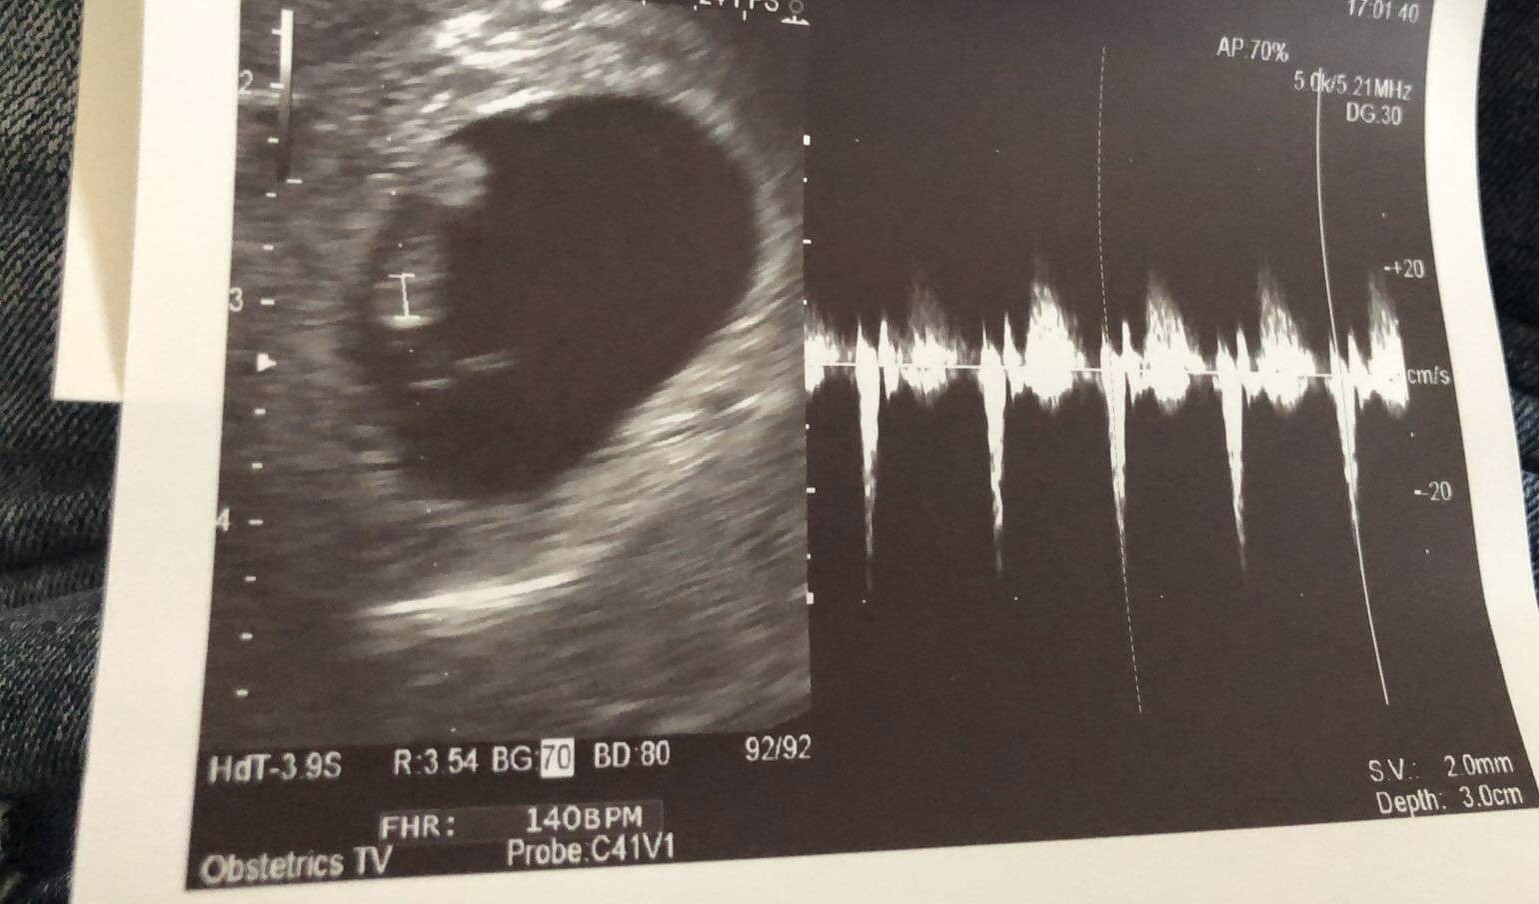

Jestem po wizycie

Wszystko dobrze, serduszko bije -140

Ma 1 cm.

Wrzucam Wam zdjęcie naszego groszka